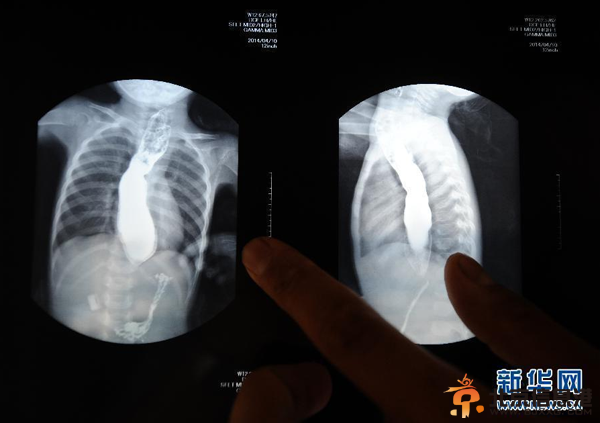

因为无钱治疗,王可然的病情恶化,胃部严重萎缩,体重仅7公斤。若不及时手术,就有生命危险。但巨额的医治费用对于这个来自太行山区的贫困家庭来说,是个难以承受的负担。图为5月22日,王志华在展示女儿一个月前拍的胸片,上面能清晰看到食管被撑得很大,食物却无法进入胃部。